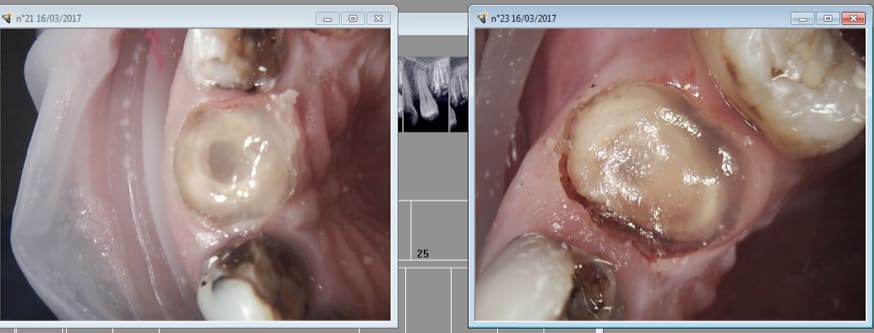

Par contre pas de provisoires, du clip flow, je tiens à la revoir la semaine prochaine pour la pose. -)))

Casa est affolée par des couronnes nitratées et des racines intactes. C'est vrai qu'avec des limes K c'est chiant de faire une endo et encore plus chiant de faire des RTE. -)))

Avant après......;

Elles on pété parce qu'elles n'ont pas été couronnées casa. -))))